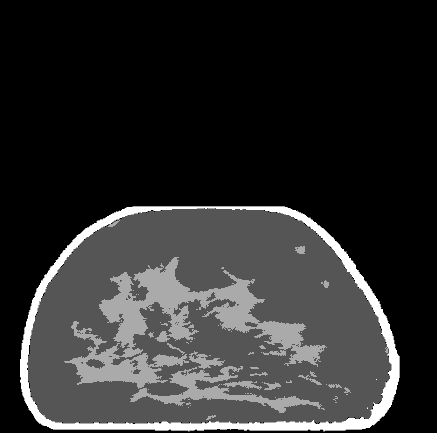

Refer to caption

(a)

(b)

(c)

(d)

Figure 9: (a) Coronal slice of a breast CT phantom, (b) MLTR reconstruction, (c) DBToR reconstruction, and (d) classification of DBToR reconstruction.

For DBToR trained on noisy virtual phantom projections and subsequently finetuned on deformed breast CT slices, where we used noise level N=8𝑁8N=8 only during training and finetuning, we summarize the reconstruction performance in Table 4, and in Figures 9, 10, and 11 we give examples of coronal, axial, and sagittal slices of the virtual breast phantom and corresponding MLTR reconstruction, DBToR reconstruction, and DBToR classification (all on noisy deformed breast CT slices). We observe that DBToR outperforms the baseline MLTR algorithm in terms of the reported metrics and visual quality of the slices, particularly noticeable for coronal and sagittal directions.